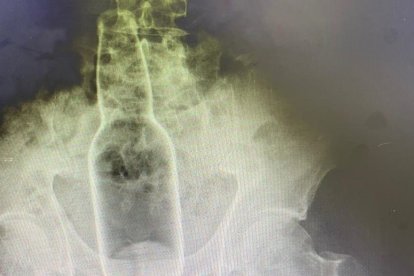

¡Hombre pasó 3 días con una botella metida en el ano!

Por vergüenza, un hombre pasó 3 días con una botella en el recto. El tipo se lo tenía calladito, pero ya no aguantaba tanto dolor. Una tomografía dio con tremendo hallazgo y al quirófano ‘de una’.

El sujeto, que no fue identificado en el reporte médico de la clínica a la que fue llevado, en Irán, tampoco reveló a los galenos lo que estaba ocurriendo hasta que una tomografía computadorizada dejó al descubierto su secreto.

Y aunque el paciente no quiso dar los detalles del suceso, en realidad fueron 18 centímetros adentro y sin vaselina.

Lo que sí se conoció, pues tenía que informarle a los médicos algunos detalles para que estos pudieran trabajar, fue que él mismo empujó el fondo de la botella hacia adentro, pensando que de esta forma podía sacarla más fácilmente agarrando la parte superior. Sin embargo, no logró lo anterior, y el objeto alcanzó el intestino grueso.

Los médicos debieron sacar la botella con cuidado, a fin de no desgarrar el recto y evitar que sufra daños en su organismo, de por sí ya ‘desvirgado’.